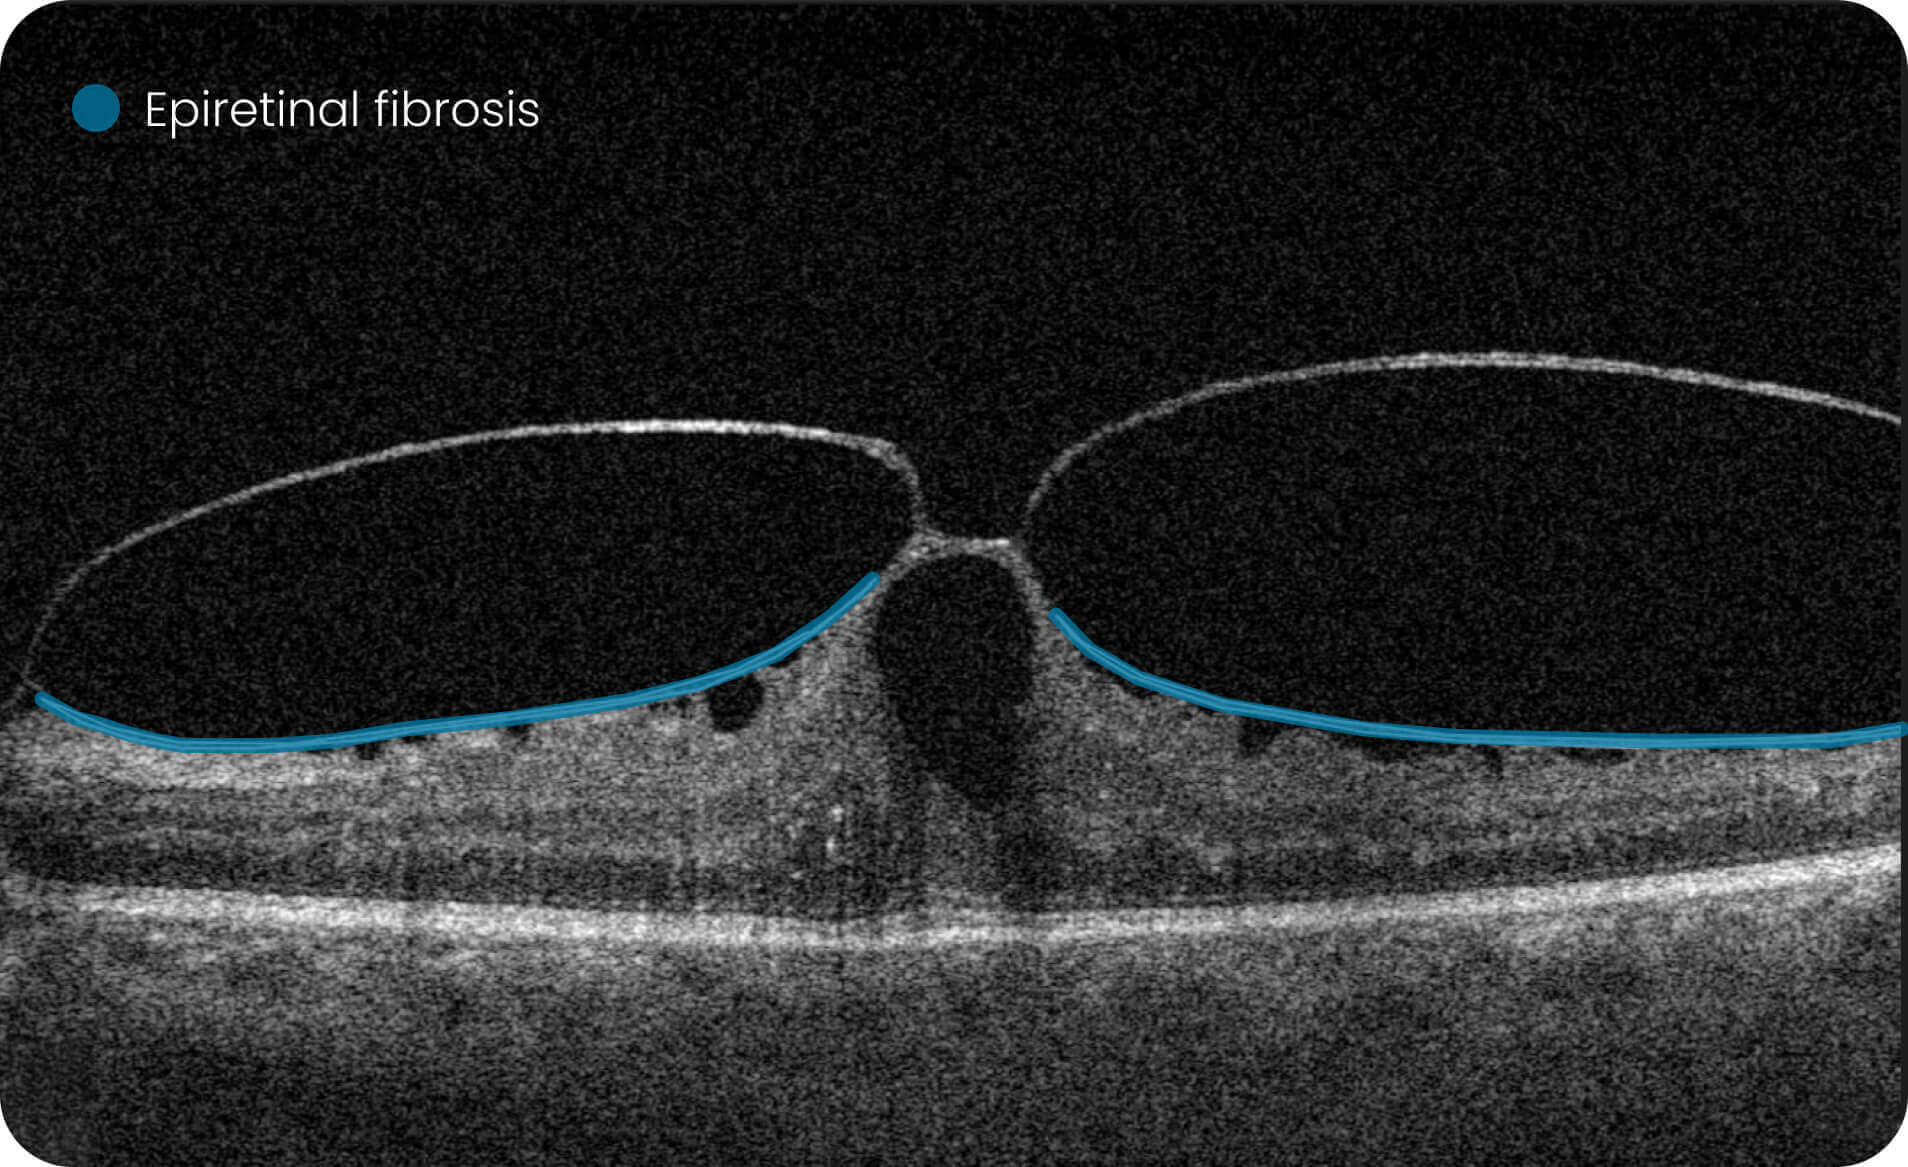

Characterization and visualization of OCT features commonly studied in Geographic Atrophy (GA), including hypertransmission, RPE atrophy, neurosensory retinal atrophy, and EZ changes.

The GA Progression feature provides tools for research-oriented visualization and comparison of OCT imaging data across multiple visits. Users can review changes in areas associated with geographic atrophy (GA) and related imaging features through percentage-based displays, maps, and graphs.

Efficient estimations of GA-associated areas designed to support research-focused image review workflows.

Quantitative, image-derived measurements of GA-related features and associated biomarkers for research analyses.

Support for research dataset stratification through calculations based on the overlap of multiple imaging-feature sets. For Research Use Only. Not for diagnostic or clinical decision-making.

Altris is a web platform developed by professionals with expertise in retinal imaging. We’ve collected a large number of OCT scans, and our team has manually annotated thousands of them to develop the Altris system, an artificial intelligence geographic atrophy research USA platform, which can: